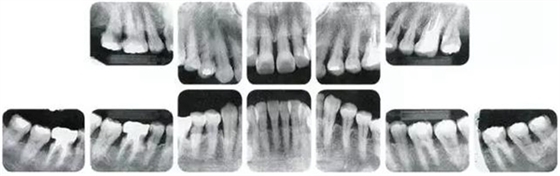

●參考病例① 35歲女性

35歲女性。妊娠4個(gè)月。過去雖然接受過刷牙指導(dǎo),但菌斑控制狀態(tài)依然不理想?;颊哂邪l(fā)現(xiàn)自己刷牙時(shí)牙齦出血。

●參考病例② 25歲女性

25歲女性。菌斑控制狀態(tài)不好。齦溝除磨牙處外全在3mm以下,X光照片上左上、右下、左下的第一磨牙上有垂直性骨吸收。這個(gè)病例是參考病例①10年前的狀態(tài),是典型的侵襲性牙周炎局部型。

牙周病的發(fā)展因部位不同而發(fā)展程度不同的。10點(diǎn)后的狀態(tài)參考病例①和參考病例②的磨牙處的狀態(tài)相比較,思考下沒接受治療病情發(fā)展的特別性吧。

參考病例① 35歲女性

在左下第一磨牙在25歲時(shí)近中處可以看到垂直性的骨吸收,但35歲時(shí)吸收停止,原本沒有見到的遠(yuǎn)中處骨吸收的,現(xiàn)在卻吸收得很嚴(yán)重。

在右下處,原本有大量骨吸收的第一磨牙處的吸收卻變緩慢,原本沒有吸收的第二前磨牙卻出現(xiàn)了吸收。出現(xiàn)吸收的左上第一磨牙的遠(yuǎn)中處,吸收得越來越多了。

把10年間的變化做成表格。牙周病的發(fā)展根據(jù)各個(gè)人會(huì)不同,即使通一個(gè)人,不同牙齒,不同牙面發(fā)展的狀態(tài)也不同。